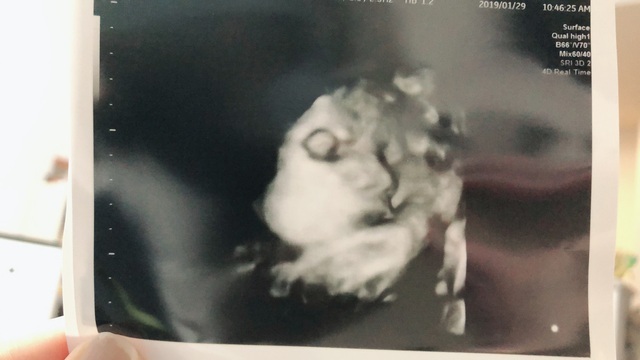

33週6日(33w6d・女の子)|しょーちゃん129 さん(27歳)

エコー写真撮影時のエピソード:

お顔がはっきり見えていることです!里帰り先の産婦人科では、4Dのエコー写真を毎回撮ってもらえる婦人科で、初めて4Dのエコー写真を見せて貰ったときの一枚です。普通のエコー写真ではわからない表情まで確認でき、こんなにしっかり育っているんだなーと感動しました!